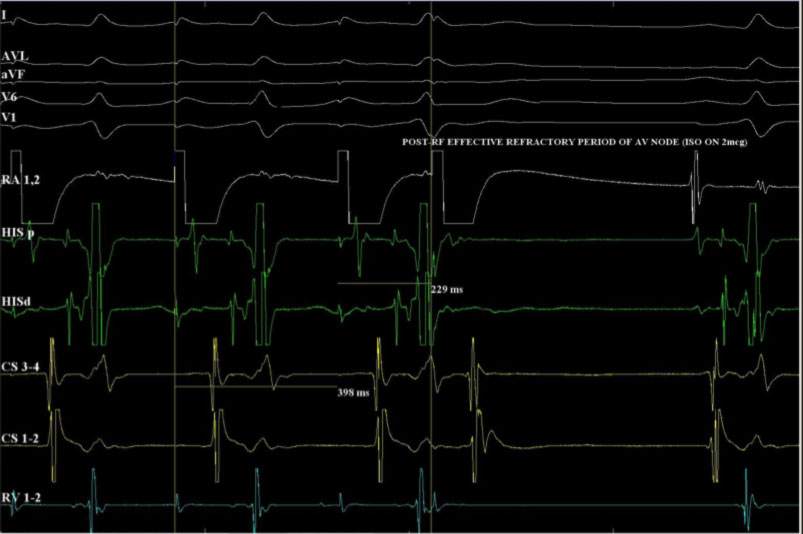

Il successo dell’ablazione è documentato dalla impossibilità di indurre l’aritmia allo studio elettrofisiologico di controllo.

L’obiettivo principale della ATC-RF è la modulazione della conduzione lungo la via lenta, bloccando il meccanismo di rientro nodale. Gli obiettivi procedurali sono riassunti nella tabella seguente: